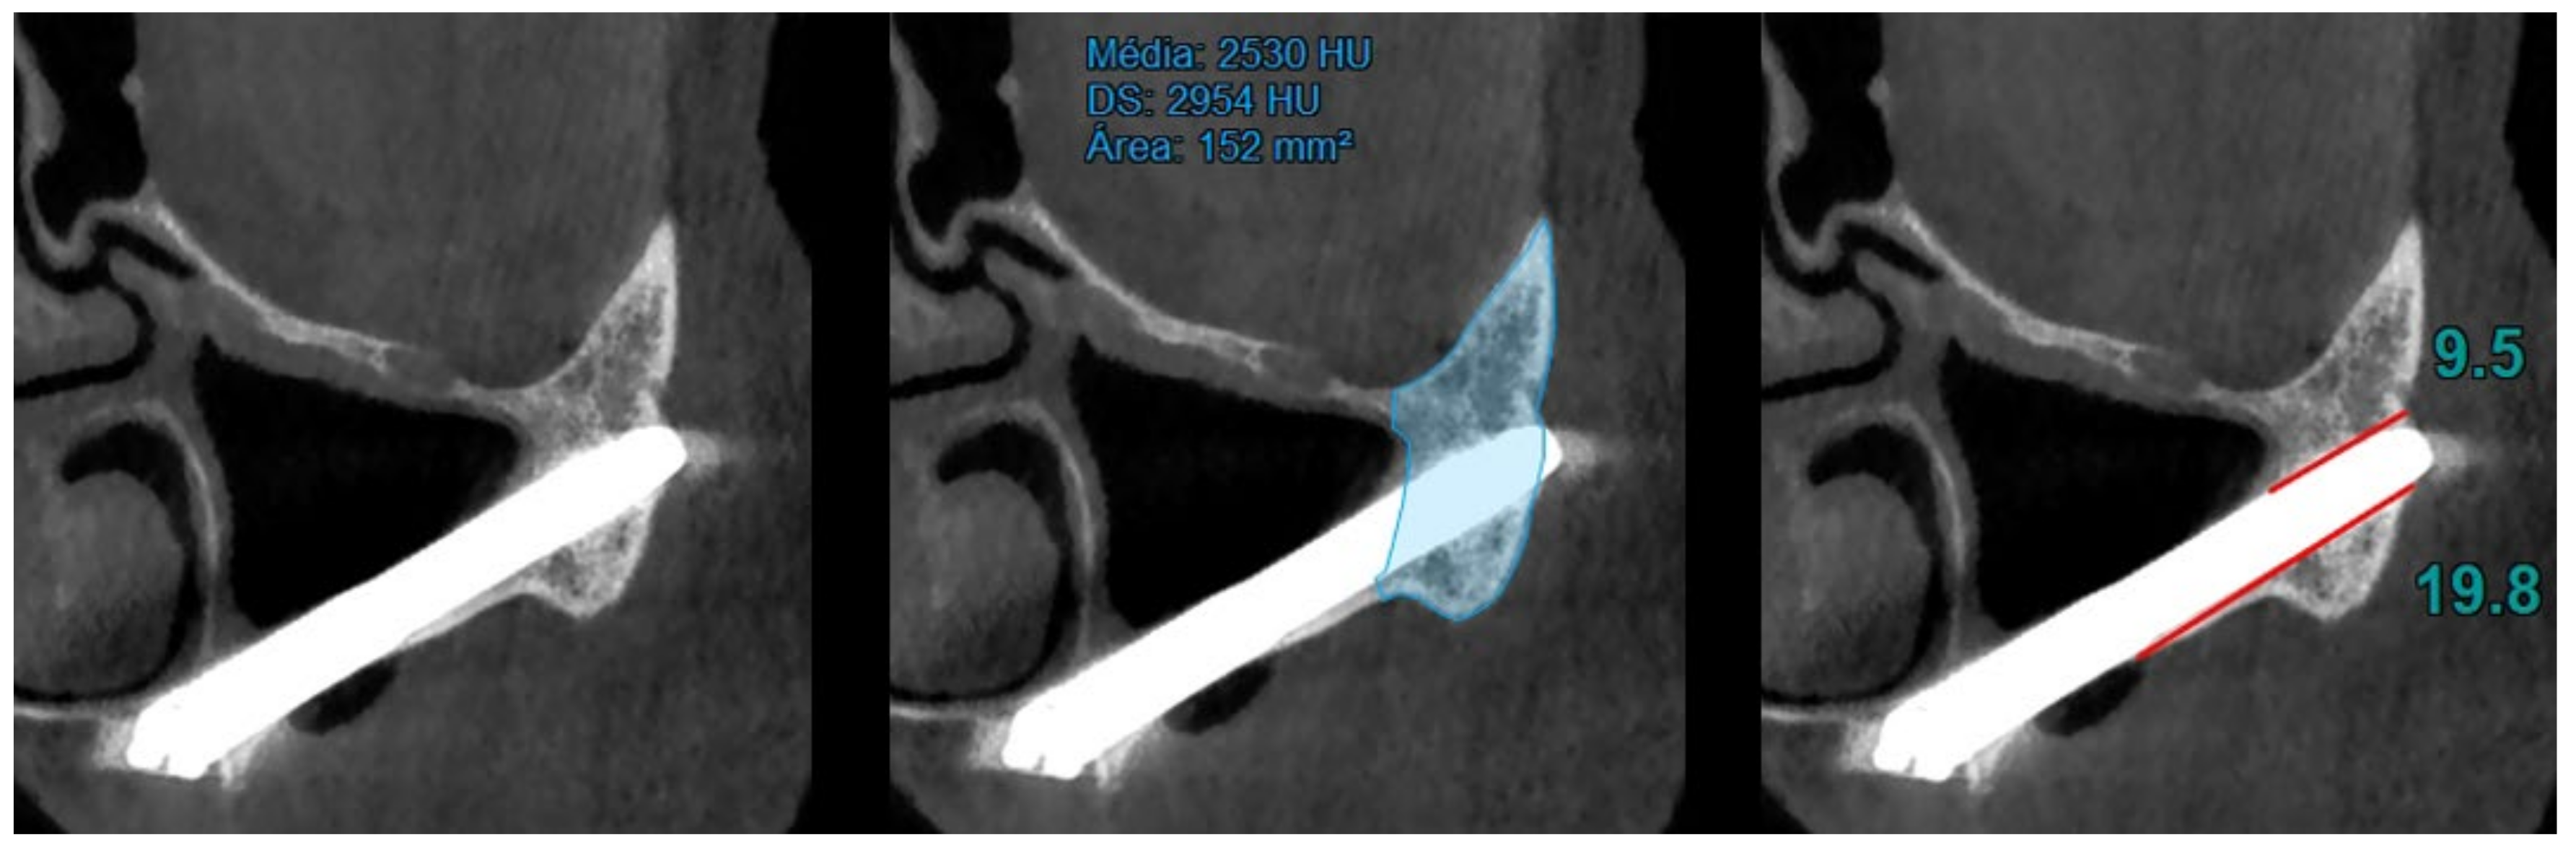

- At T1 (12 months of follow-up), the area and density of the zygomatic bone, the upper contact distance between the zygomatic bone and the zygomatic implant, and the lower contact distance between the zygomatic bone and the zygomatic implant were evaluated (Figure 2).

| Zygomatic Bone Density (1st Quadrant) (HU) Mean ± SD, Newtons | T0: 1077.23 ± 264.90; T1: 2642.06 ± 550.33; T2: 2853.04 ± 530.26. |

| Zygomatic Bone Density (2nd Quadrant) (HU) Mean ± SD, Newtons | T0: 1030.46 ± 314.13; T1: 2457.86 ± 561.85; T2: 2696.60 ± 583.29. |

| Upper Contact Distance between Zygomatic Bone and Zygomatic Implant (1st Quadrant) (mm) Mean ± SD, Newtons | T0: No valid cases; T1: 9.01 ± 3.19; T2: 9.10 ± 3.23. |

| Upper Contact Distance between Zygomatic Bone and Zygomatic Implant (2nd Quadrant) (mm) Mean ± SD, Newtons | T0: No valid cases; T1: 8.04 ± 3.02; T2: 8.20 ± 3.19. |

| Lower Contact Distance between Zygomatic Bone and Zygomatic Implant (1st Quadrant) (mm) Mean ± SD, Newtons | T0: No valid cases; T1: 13.70 ± 4.74; T2: 13.61 ± 4.62. |

| Lower Contact Distance between Zygomatic Bone and Zygomatic Implant (2nd Quadrant) (mm) Mean ± SD, Newtons | T0: No valid cases; T1: 14.69 ± 4.96; T2: 14.65 ± 4.98. |